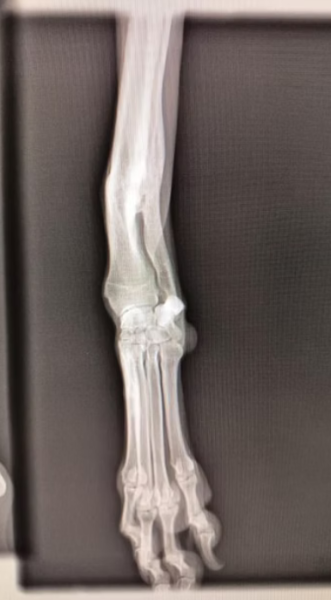

Ich bin Electra. Wie viele andere Hunde hier, bin ich eine ausrangierte Jagdhündin. Leider war mein Vorderlauf gebrochen. Dies ist aber problemlos verheilt und es muss auch nicht operiert werden. Trotzdem war dies wohl Grund genug mich einfach auf die Strasse zu setzen.